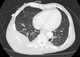

Chest mass

A chest radiograph, called a chest X-ray (CXR), or chest film, is a projection radiograph of the chest used to diagnose conditions affecting the chest, its contents, and nearby structures. Chest radiographs are the most common film taken in medicine. [Source: Wikipedia ]